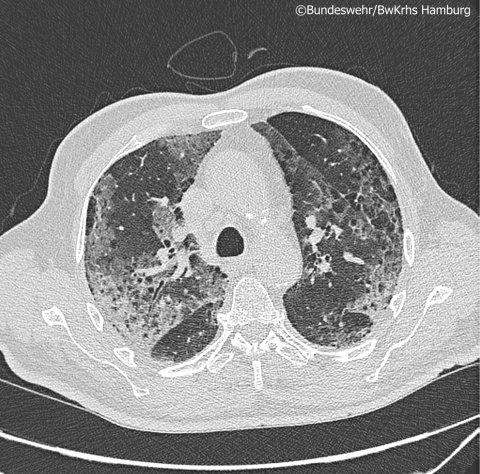

MehrSteigendes hsTroponinT im Rahmen von COVID-19:

Perimyokarditis oder asymptomatische Myokardischämie?